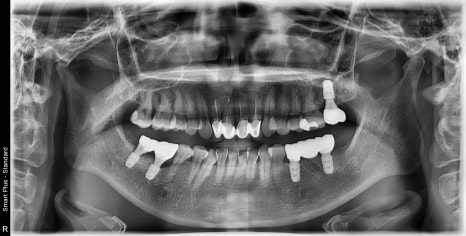

왼쪽 치아 발치 후 임플란트 수술 후 보철까지 완성되었습니다.

다행히 오른쪽은 쓰러져있는 어금니들이 위 어금니를 받쳐주고 있어 교합의 변화가 크지 않아 기존 충치치료만 진행하고, 아래 부위만 임플란트 수술이 진행되었습니다.

치아가 쓰러져있는 공간이 매우 컸기 때문에 임플란트 주변의 빈 공간에 치조골 이식술을 동반하여

임플란트 주변에 뼈를 보강해 주는 작업까지 진행되었습니다.

수술을 나눠서 하고 오른쪽은 왼쪽에 비해 수술 기간이 길어져서 총 치료 기간이 길어질 수밖에 없었지만 환자분께서 잘 따라와 주셔서 잘 마칠 수 있었던 것 같습니다.

결과론적으로만 보면 수술 자체는 그렇게 힘든 수술은 아닙니다.